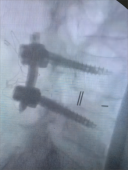

2.颈椎后路减压固定技术

颈椎后路减压技术适用于:脊髓型颈椎病伴发育性或多节段退变性椎管狭窄者;多节段OPLL;颈椎黄韧带肥厚或骨化所致脊髓腹背受压者。有节段性不稳定者可以同时行侧块钛板螺钉或经椎弓根螺钉内固定、植骨融合术。我科在区域内率先开展颈椎单开门、双开门技术,颈椎椎板切除减压椎弓根内固定术,均获得满意疗效。